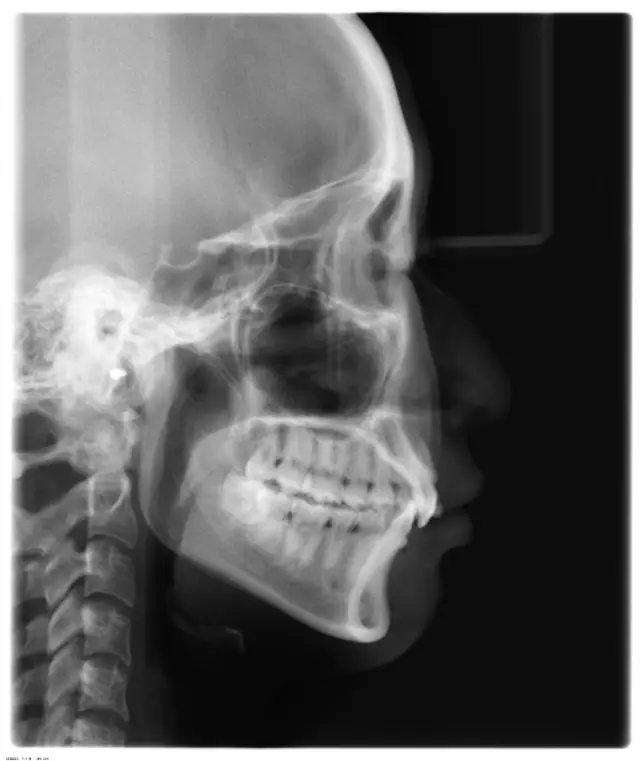

Damon 病例分享:安氏 II 類二分類露齦笑的矯治(董一磊)

患者信息